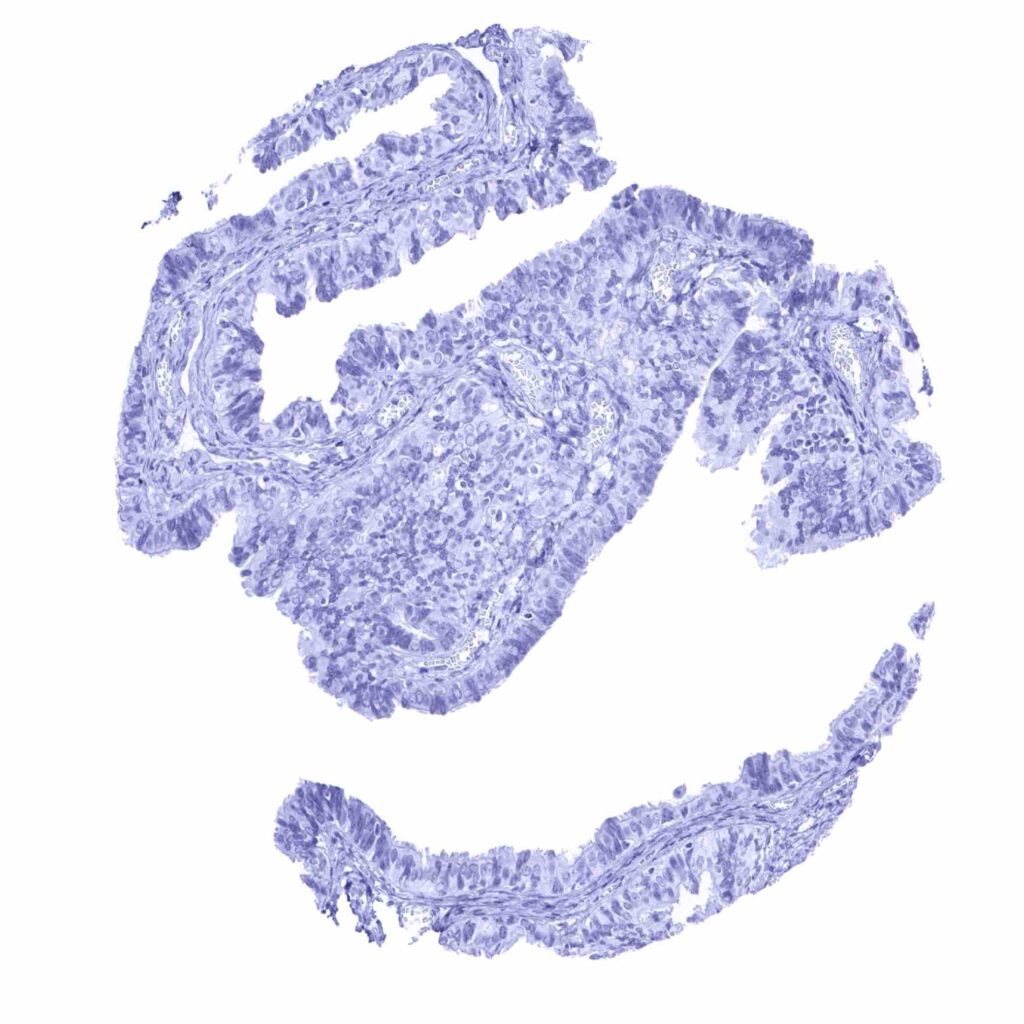

Fallopian tube, mucosa